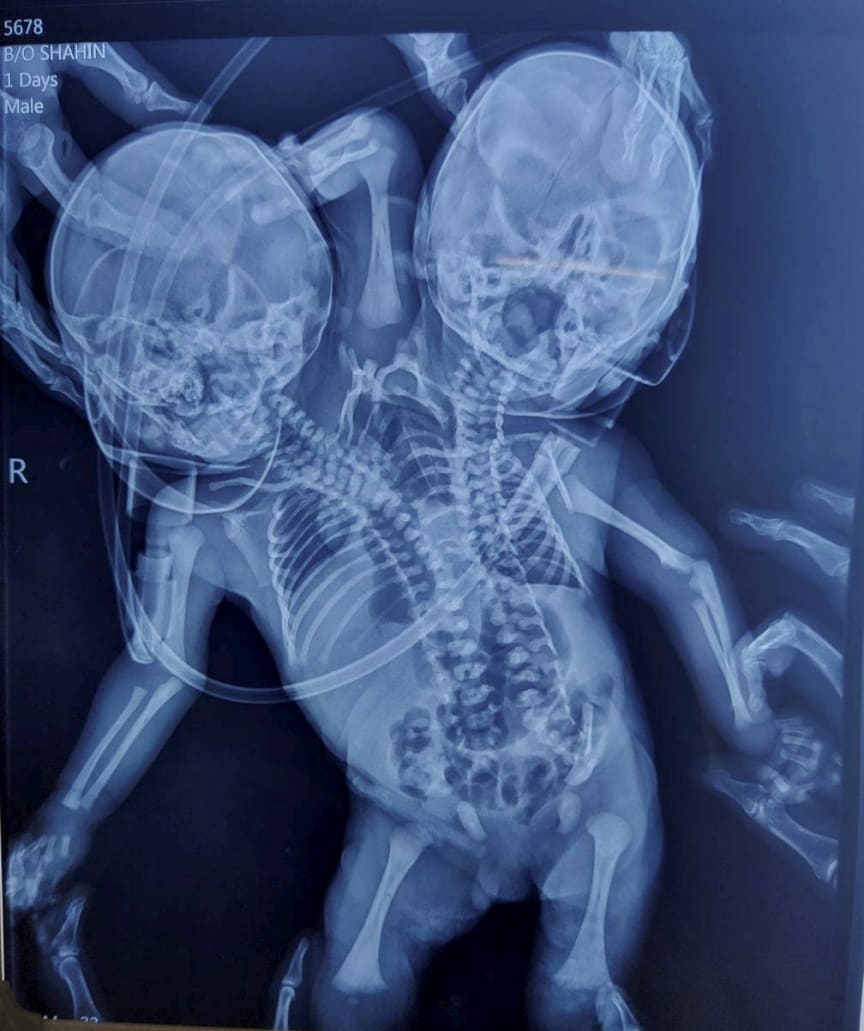

In Indien wurde am 28. März ein Kind mit zwei Köpfen geboren.

Neu-Delhi. "Solche Fälle sind selten und der Zustand der Babys ist vor allem in den ersten Tagen ungewiss. Deshalb haben wir sie unter Beobachtung. Eine Operation ist nicht geplant", sagte Dr. Lahoti, sagte laut "Daily Mail" über die Geburt eines Babys mit zwei Köpfen im indischen Bundesstaat Madhya Pradesh. Das Kind wurde am 28. März geboren und die Ärzte in einem Krankenhaus in der Stadt Ratlam geben dem Neugeborenen geringe Überlebenschancen, da auch eine Operation zur Trennung der siamesischen Zwillinge nicht möglich zu sein scheint.

Das Baby wurde mit zwei Köpfen, zwei Wirbelsäulen, zwei Herzen und drei Armen geboren.